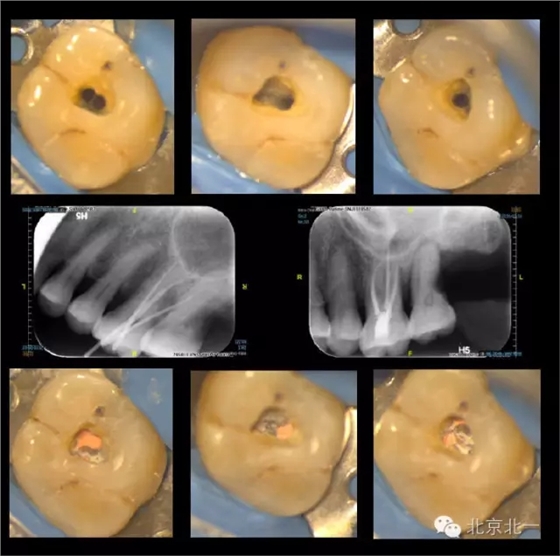

再看我們的現(xiàn)實,在我們的日常工作中,也一直期望能對微創(chuàng)開髓多有嘗試,可惜的是由于我國患者的口腔保健意識還有待提高,很多來牙髓病專科就診的患者牙體本身由于病變已沒有微創(chuàng)的可能。前段時間終于等到了這么一例牙周牙髓聯(lián)合病變,患者有著強烈的保留牙齒的愿望,但在牙周治療中并發(fā)了牙髓炎的癥狀,因此轉(zhuǎn)診至牙體牙髓??菩枰M行根管治療。

對于這個冠部牙體組織完好的病例,我們也確實想給她盡量保留健康組織,于是就開始了對這個病例的微創(chuàng)治療。

根充完成后,用樹脂對牙齒進行了充填(由于是急診患者,很遺憾忘了拍攝術(shù)前照)。